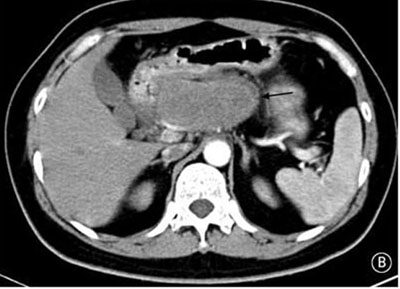

就診時實驗室檢查結果顯示嚴重高血糖(血糖水平為982mg/dL[55mmol/L])。腹部CT檢查顯示胰頭部位出現(xiàn)一個9cm大小的腫塊(如圖B箭頭所示)??崭寡逡雀哐撬厮綖?30pg/ml(正常值≤80pg/ml)。